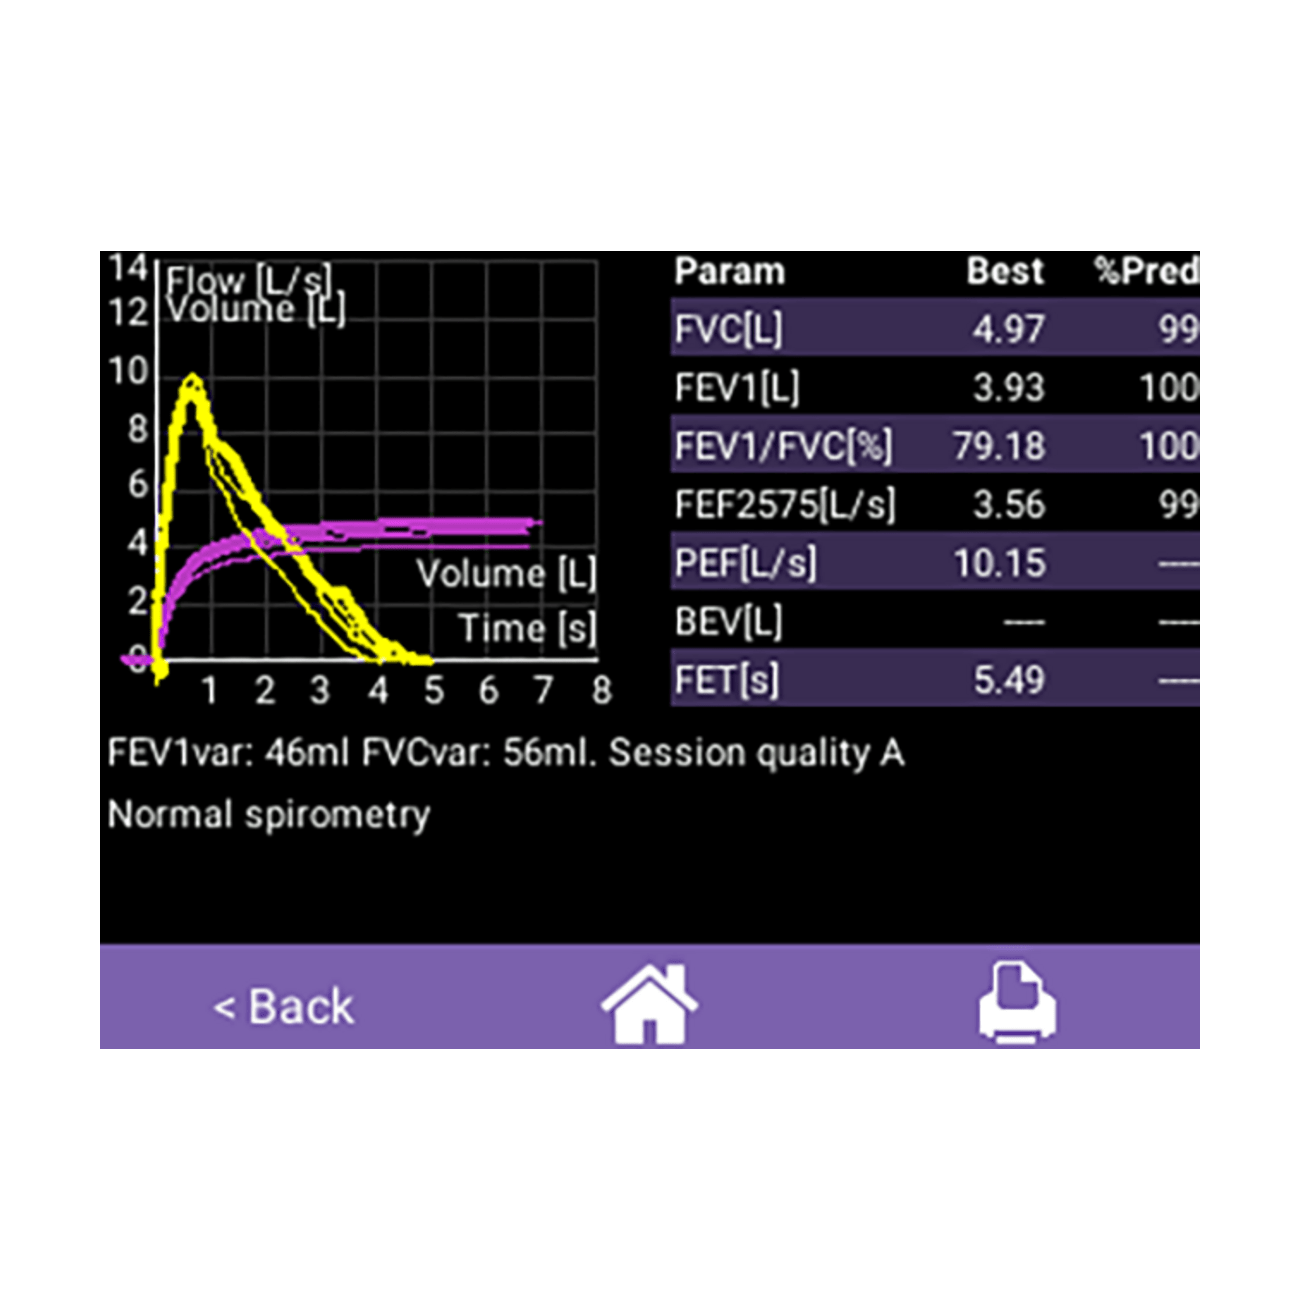

- Großer Farb-Touchscreen

- für bequeme Dateneingabe und farbige Kurven- und Datendarstellung